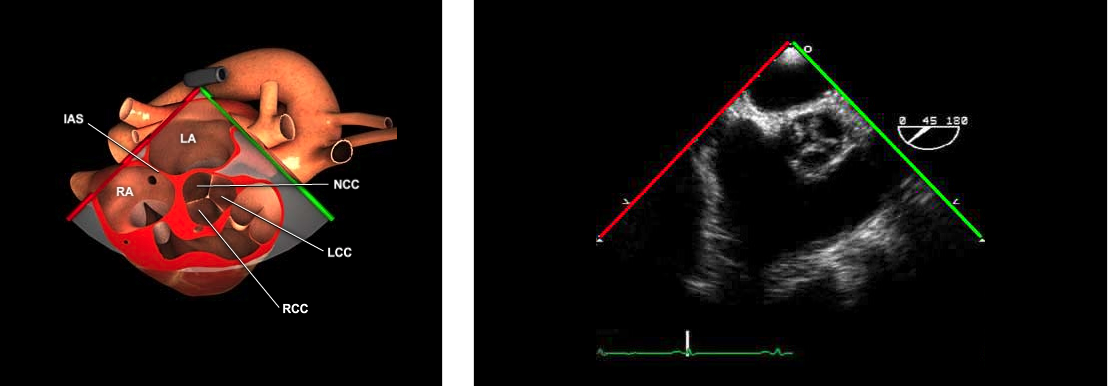

Identify every structure in the ME AV SAX view:

LA

IAS

RA

LA

Coronary Ostia

In the ME AV SAX view (30-45°) the image plane is directed thru the LA and aligned parallel to the AV annulus.

All three aortic cusps should appear symmetrical.

The non-coronary cusp of the aortic valve is adjacent to the inter atrial septum

The right coronary cusp is most anterior

The left coronary cusp is adjacent to the pulmonary artery.